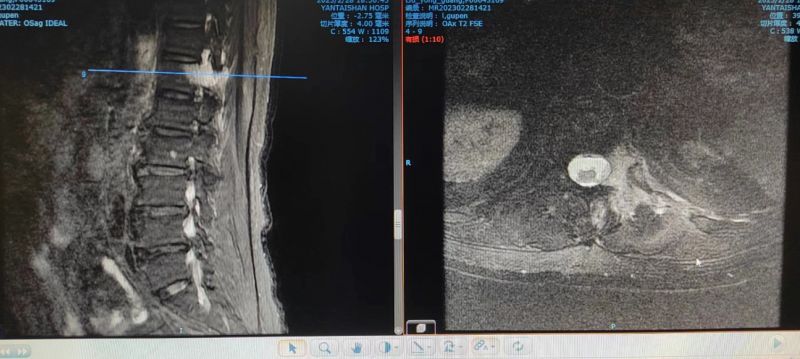

疼痛科高建东团队对刘大爷的病情进行综合评估,考虑患者目前肿瘤多发转移状况,家属难以接受手术切除方案,放化疗短时间内无法解决疼痛问题,综合考虑后制定了行腰1、2背根神经节脉冲射频消融的治疗方案,调制神经消除神经水肿,力求用最快的速度达到最好的止痛效果。这种治疗方案比普通的椎间盘突出射频消融要复杂的多,因为这种方案的进针针尖要尽可能靠近神经根才能对神经有调制作用,又不能过近损伤神经,鉴于老人痛苦度极高,方案确定后当天下午即刻实施治疗方案,术前利用C型臂导视下定位进针点和进针路线,顺利地将射频针精准放至射频靶点,连接电极、测试、复制患者疼痛症状后,给与42℃下脉冲射频模式2分钟,整个过程用时35分钟,治疗结束后刘大爷的疼痛很快消失了。刘大爷笑道,“今晚终于可以睡个好觉了。”停服止痛药物,观察36小时患者疼痛症状无反复,顺利出院。

QQ截图20230313151555.png

C型臂透视射频针穿刺到靶点位置。